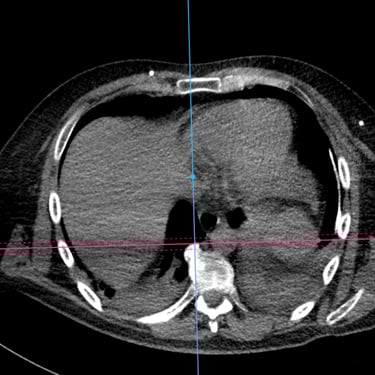

Hidrocefalia y Disfunción de Derivación: Colocación de Derivación Ventrículo-Pleural

La hidrocefalia puede complicarse cuando la derivación ventrículo-peritoneal deja de funcionar correctamente, produciendo aumento de la presión intracraneal y síntomas como cefalea, vómitos, somnolencia o deterioro neurológico. Cuando el peritoneo deja de ser una opción viable debido a infecciones, cirugías previas o mala absorción, se considera la derivación ventrículo-pleural como alternativa efectiva. Este procedimiento permite redirigir el líquido cefalorraquídeo hacia la cavidad pleural, donde puede ser absorbido adecuadamente. La intervención oportuna restablece el drenaje del LCR, reduce la presión intracraneal y mejora el pronóstico del paciente, siendo una solución segura en casos de disfunción peritoneal.